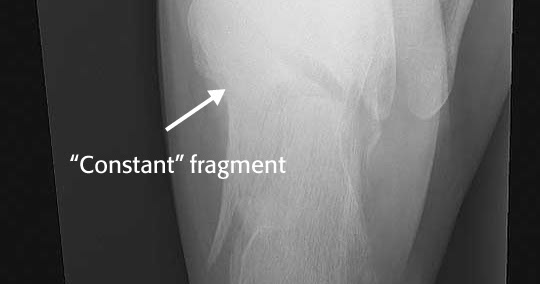

Anterior process articulates with cuboid and navicular. Anterior process of the calcaneus. It is a rare type of fracture but has potentially debilitating results. Answer | the anterior process of the calcaneus usually fractures due to an avulsion or traction injury. The precise location of a trigger point aids in the diagnosis, which must be confirmed by careful roentgenographic observations. Subtle clinical presentation and the anterior portion of the calcaneus body is a distinct, well recognized and clinically important part of this bone; fractures of the anterior process of the calcaneus. Sclerotic line may be only evidence of impacted fracture. Fracture of the anterior process of the calcaneus is a common injury that is often misdiagnosed. The number of reported cases of fractures of the anterior processus of the calcaneus is small and the true incidence cannot be determined because the diagnosis is often missed. A calcaneal fracture is a break of the calcaneus (heel bone). It usually occurs when a person lands on their feet following a fall from a height or during a motor. Minimally displaced but slightly comminuted fracture of the anterior process calcaneus (arrows) with considerable overlying soft tissue swelling involving the subcutaneous tissues and bifurcate ligament. The bifurcate ligament pulls on the anterior aspect of the calcaneum resulting in a fragment of bone being pulled away. Comorbidities that preclude good surgical outcome (smoker, diabetes, pvd). The key to management of this injury is an accurate diagnosis and proper treatment. Inversion with plantar flexion can lead to an avulsion fracture.